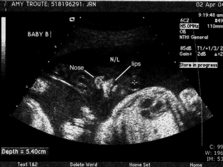

At one point we were able to get face-to-face with Baby B... It was yawning and touching its face cute little lips and nose and chin... I got all teary, Reese grabbed my hand what a moment!! Baby A was facing my back so we didnt get to see its face bummer! Stubborn little thing! Maybe well see its face at next months ultrasound were supposed to have one each month that remains... Yay!